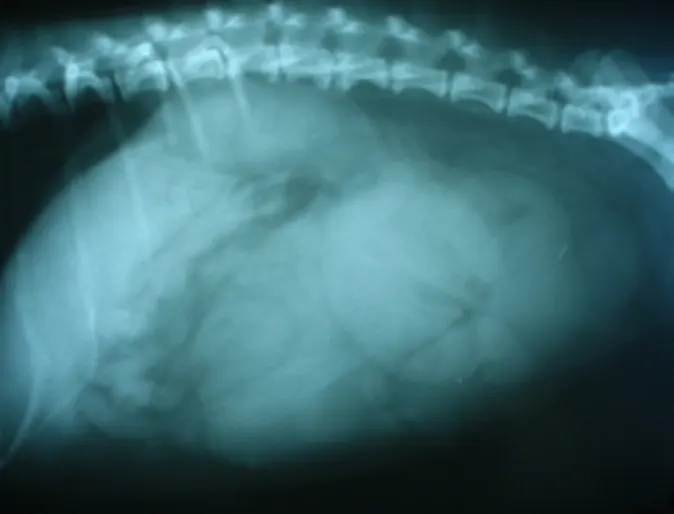

Enormous Tumor on a Spleen

Moses is a 8 year old Labrador Retriever who was slowly gaining weight for almost a year. Moses actually started appearing like a pregant dog before seeing us which is hard to do for male dog. He also started to become quite lethargic and he stopped eating.